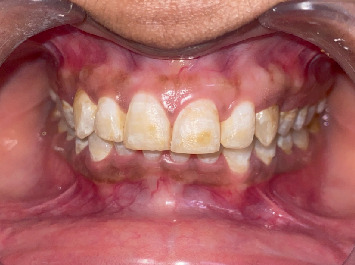

牙齿变色,特别是由于氟中毒,提出了一个显着的审美挑战,许多患者。本文探讨了牙齿漂白和牙釉质微磨损联合使用作为治疗氟中毒引起的变色的有效方法。牙齿漂白是一种广泛应用于减轻外在和内在污渍的方法,在改善变色牙齿的整体外观方面显示出良好的效果。牙釉质微磨蚀,包括机械去除表面牙釉质污渍,可以通过解决更严重或更顽固的变色来提高漂白的有效性。本文综述了这些治疗的机制,它们的临床适应症,以及它们在不同程度的氟牙症患者中的结果。此外,还讨论了潜在的副作用,如牙齿敏感和牙釉质损伤,并强调了减少这些风险的策略。通过结合这些方法,临床医生可以为寻求氟牙美容改善的患者提供更全面,个性化的护理,同时关注美观结果和长期牙齿健康。

Dental discoloration, particularly due to fluorosis, presents a significant aesthetic challenge for many patients. This article explores the combined use of dental bleaching and enamel microabrasion as effective treatments for managing fluorosis-induced discoloration. Dental bleaching, a widely used method for lightening extrinsic and intrinsic stains, has shown promising results in improving the overall appearance of discolored teeth. Enamel microabrasion, which involves the mechanical removal of superficial enamel stains, can enhance the effectiveness of bleaching by addressing more severe or resistant discoloration. The article reviews the mechanisms of these treatments, their clinical indications, and their outcomes in patients with varying degrees of dental fluorosis. Additionally, potential side effects, such as tooth sensitivity and enamel damage, are discussed, emphasizing strategies to minimize these risks. By combining these methods, clinicians can offer more comprehensive, individualized care for patients seeking cosmetic improvements for fluorotic teeth, with attention to both aesthetic outcomes and long-term dental health.